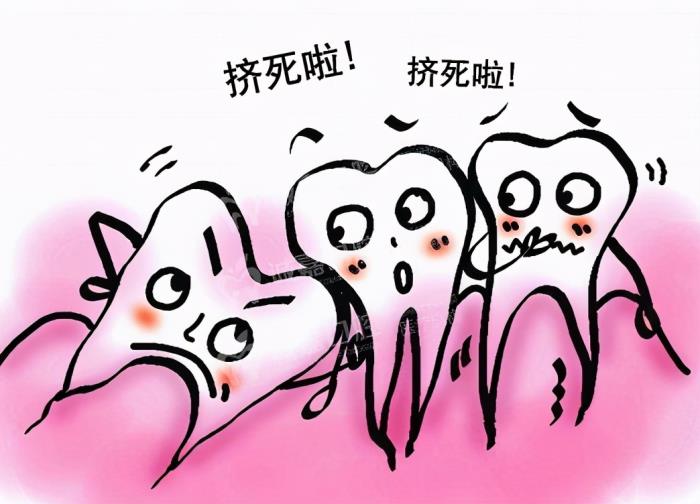

侵犯到邻牙的智齿。

这类智齿大多数直接是不知道的,只能由医生拍牙片来检查确诊。由于智齿萌出的空间不足,导致智齿倾倒在第二大臼齿上,出现清洗不易、牙齿吸收的现象,会导致患者出现不适、牙疼。因此也是主张拔掉的!

不易清洁的智齿

因为空间不足的关系,大多数智齿都长得东倒西歪,。从而构成清洁困难的现象,导致智齿龋坏、发炎等。

阻生齿

这是最难搞的一种,对于医生来说很棘手!阻生齿一般是埋伏在牙槽骨内,通常需要拍牙片才能得知,假如出现疼痛等病灶,就需要及时采取拔除措施了。